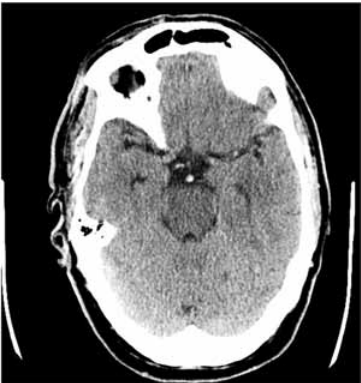

Paciente do sexo masculino, 67 anos, apresentou-se ao hospital com rebaixamento súbito da consciência há uma hora da admissão. Ao exame apresentava tetraparesia flácida, sonolência e nistagmo vertical. Após estabilização hemodinâmica, realizou tomografia de crânio (a seguir). Familiar que acompanha o paciente refere que ele faz uso de medicações para hipertensão arterial e arritmia cardíaca, mas não sabe informar os nomes.

Assinale a alternativa que apresenta, corretamente, o tratamento mais adequado para esse paciente.